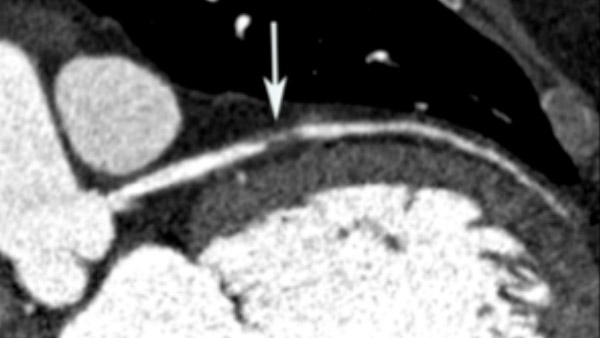

The Cardiovascular Imaging Research Center (CIRC) @ MGH and HMS brings together a group of researchers that are using advanced cardiovascular imaging to improve patient health. CIRC creates new opportunities to use the combined power of AI and Imaging for biomarker discovery and improvements in population health, multisystem imaging to unlock the secrets of how external stress leads to brain activation that advances atherosclerosis, and how to address the excess risk of cardiovascular disease among patients with cancer.